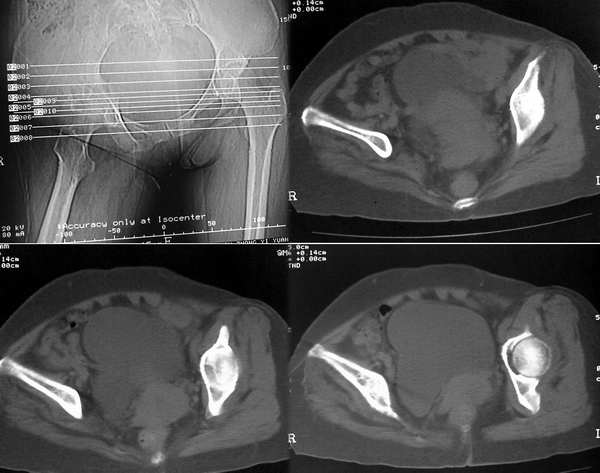

患者,女,48岁,右髋关节疼痛半年余,现行走跛行,7月份x线片提示两上肺结核。

十二月九号ct片

七月份胸片示双肺大小不等结节状高密度影,右侧为著,边界清晰;右上纵隔阴影增宽。十二月份胸部平片未见明显异常。七月份髋关节片示双侧髋关节不对称,左髋关节抬高;右侧髋臼及股骨头密度减低,髋臼见蜂窝状低密度影,髋关节外侧软组织影增宽,边界尚清晰。十二月份髋关节示左髋关节抬高更明显,髋臼顶及髋臼窝加深、内陷,骨盆变形。ct片示右髋臼不规则骨质破坏,呈蜂窝状,右股骨头密度减低,髋关及周围软组织肿胀,髋关节积液。考虑:右髋关节结核合并关节中央型半脱位。

影像表现:右髋关节股骨头及髋臼上缘骨质虫蚀样破坏,所谓“唇吻状”骨质破坏,关节间隙变窄,关节囊肿胀。

右侧髋关节间隙变窄,右髋臼不规则多发囊状骨质破坏,右股骨头密度减低,边缘毛糙,并见虫蚀样破坏,髋关节周围软组织肿胀,髋关节积液。考虑:右髋关节结核